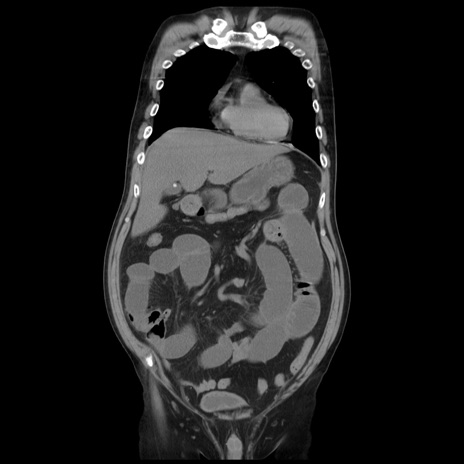

矢状断像